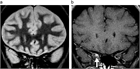

1. MRIのSTIR法は、視神経炎の病態把握に有用で推奨される(推奨度1)

1. 視神経炎の活動性炎症の有無はMRIのT1強調画像脂肪抑制造影で判断する(推奨度1)